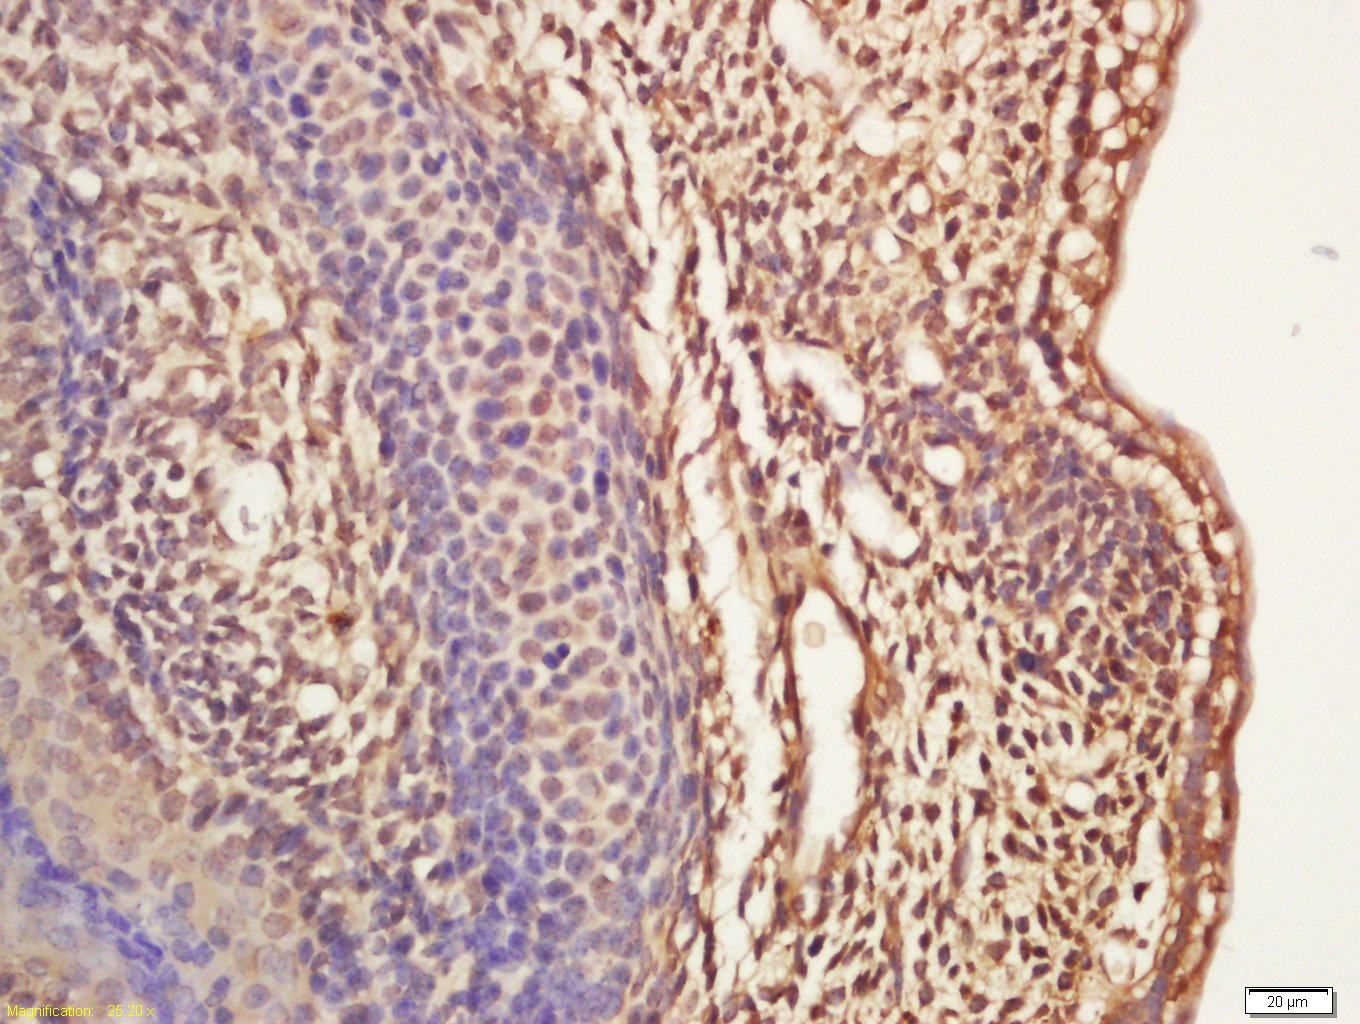

Antigen retrieval: citrate buffer ( 0.01M, pH 6.0 ), Boiling bathing for 15min; Block endogenous peroxidase by 3% Hydrogen peroxide for 30min; Blocking buffer (normal goat serum,C-0005) at 37℃ for 20 min;

Incubation: Anti-MASH1 Polyclonal Antibody, Unconjugated(bs-1155R) 1:200, overnight at 4°C, followed by conjugation to the secondary antibody(SP-0023) and DAB(C-0010) staining